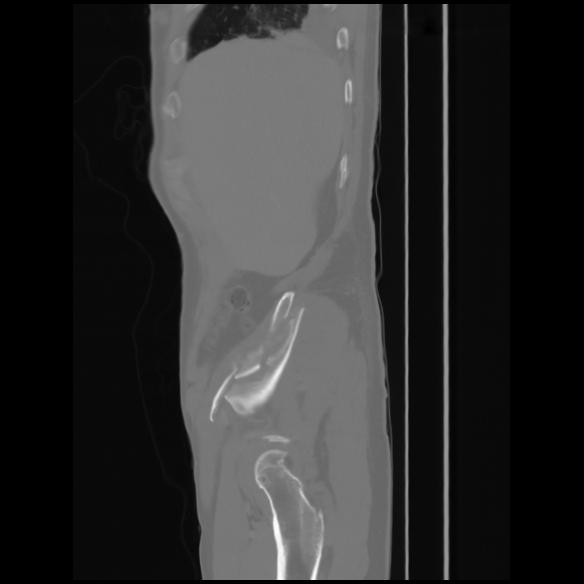

7 CUERPO,CE,Sagittal,3.000,CUERPO,Sagittal,